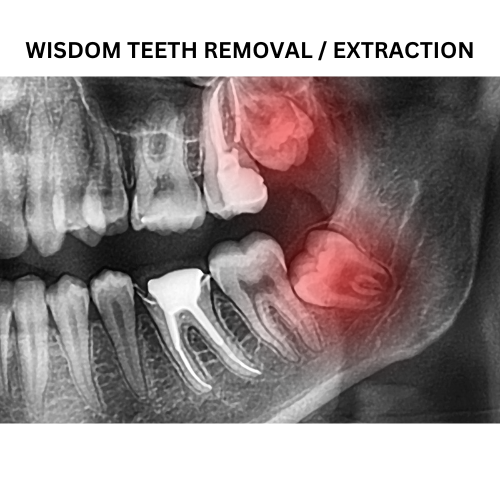

Wisdom tooth removal, jaw correction surgeries, cyst removal, trauma management, and pre-prosthetic surgeries.Prosthodontics (Crowns, Bridges & Dentures)

Extractions

Our experienced Dentists perform Gentle and Stress-Free Extractions, utilizing precise Techniques to ensure minimal discomfort and promote speedy recovery.